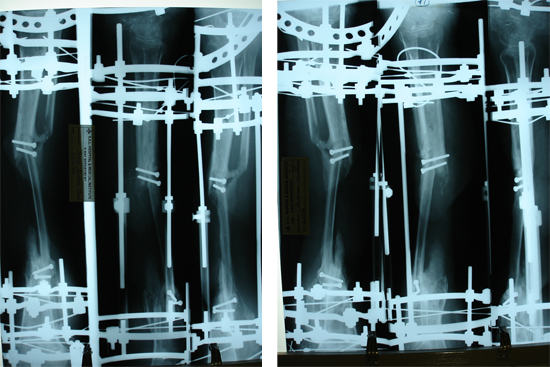

Tibialisation Of Fibula

Shankar Giri

Sudama